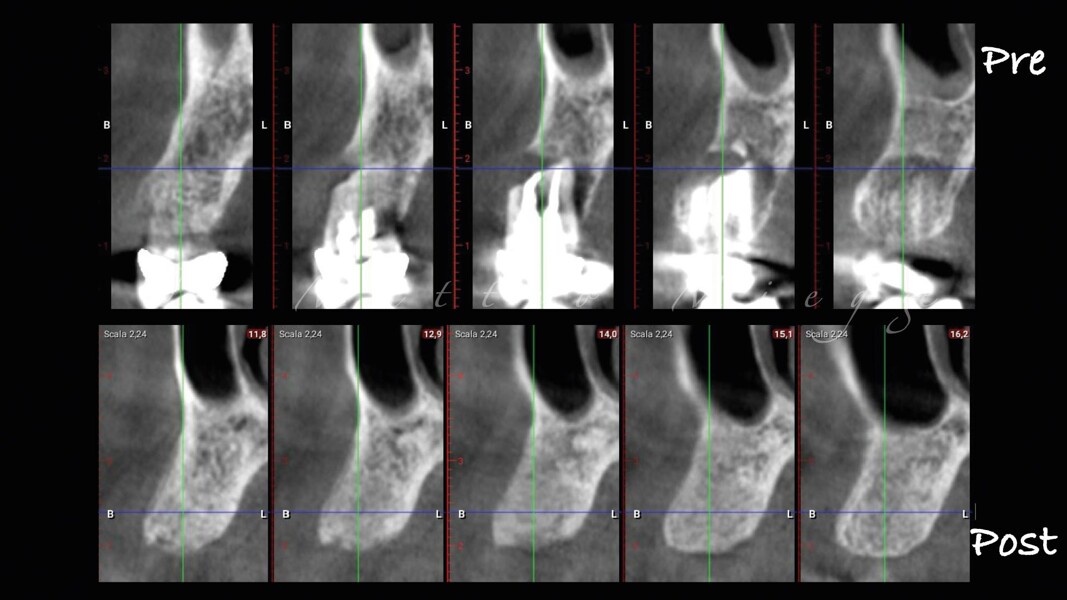

Una paziente di 50 anni presentava un premolare superiore non recuperabile. Dopo CBCT preoperatoria (T0) (Fig. 1), si è proceduto all’estrazione atraumatica e alla gestione dell’alveolo mediante posizionamento vestibolare di una membrana corticale eterologa (Lamina fine 0,7 mm, 35 × 15 mm, OsteoBiol) e riempimento con spugne di collagene (Figg. 2, 3). Sono stati applicati punti di sutura in nylon non riassorbibile 4/0. Dopo sei mesi di guarigione, una nuova CBCT (T1) ha consentito la valutazione della qualità ossea. Per la fase implantare è stato eseguito un lembo secondo la tecnica del roll flap, con preservazione delle papille interdentali e aumento del tessuto cheratinizzato (Fig. 4). È stato inserito un impianto JD Evolution Plus (4,3 × 11,5 mm) ottenendo un’eccellente stabilità primaria. Durante la chirurgia è stato prelevato un campione osseo per analisi istologica (Fig. 5).  Il lembo è stato suturato con nylon 4/0 intorno all’abutment di guarigione. Dopo due mesi, la paziente è stata riabilitata con una corona monolitica in zirconia realizzata da impronta digitale intraorale (Fig. 6).

Il protocollo chirurgico ha seguito i principi della tecnica LAR, prevedendo una gestione stratificata dei materiali rigenerativi al fine di ottenere stabilità volumetrica e controllo biologico del sito post-estrattivo. La membrana ossea eterologa ha fornito un supporto rigido e stabile per la rigenerazione ossea e il mantenimento dei contorni alveolari. Le spugne di collagene sono state scelte per la loro biocompatibilità e capacità di favorire emostasi e rigenerazione tissutale. Le misurazioni dello spessore osseo sono state effettuate su CBCT a T0 e T1 in tre punti:

1. porzione coronale;

2. terzo medio;

3. terzo apicale.

L’analisi CBCT ha evidenziato un mantenimento del volume osseo con valori comparabili tra T0 e T1.

• T0: larghezza 9,22 mm, altezza 17,12 mm;

• T1: larghezza 9,46 mm, altezza 17,02 mm.